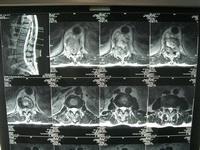

根据病史、体征和X线摄片表现,必要时辅以CT可作出诊断。但是,早期病例,椎旁无脓肿和窦道,其它部位无结核病变者,诊断较为困难。

1.X线摄片 脊椎X线正位摄片必要时也可照斜位片表现分别说明如下:

(1)椎弓根病变 椎体上部棘突上方两侧圆形椭圆形影像,不对称的溶骨性破坏模糊不清者。

(2)椎板病变 棘突两旁骨质密度低。

(3)棘突病变:与上下正常棘突比较原有棘突部分或全部阴影消失者。